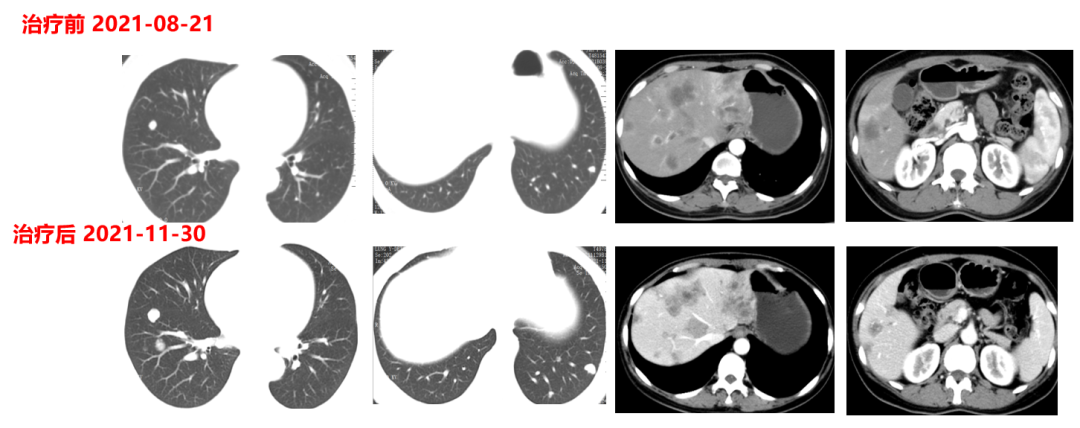

肿瘤初次进展(2021-11-30)

患者于2021年11月30号复查时,肺上病灶增大增多,肝脏病灶稍增大,肿瘤标志物增高,整体疗效评价PD,考虑一线治疗进展。

于2021-12-03、2021-12-27给予伊尼妥单抗+吡咯替尼方案治疗2周期。2022.1.19始给予患者伊尼妥单抗+吡咯替尼+替雷利珠单抗治疗,两周期,四周期时的疗效评估可以看到,肺上病灶明显缩小,甚至有的病灶消失,肿瘤标志物也在持续下降。